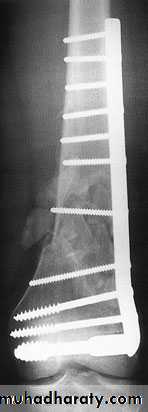

Treatment:

Undisplaced fractures

treated conservatively:

Haemarthrosis aspiration and compression bandaging,

above knee cast for one months

For displaced fractures

treatment is by open reduction and internal fixation with

plate and screws as it is an intra articular fracture.

fixation of tibial plateau fracture